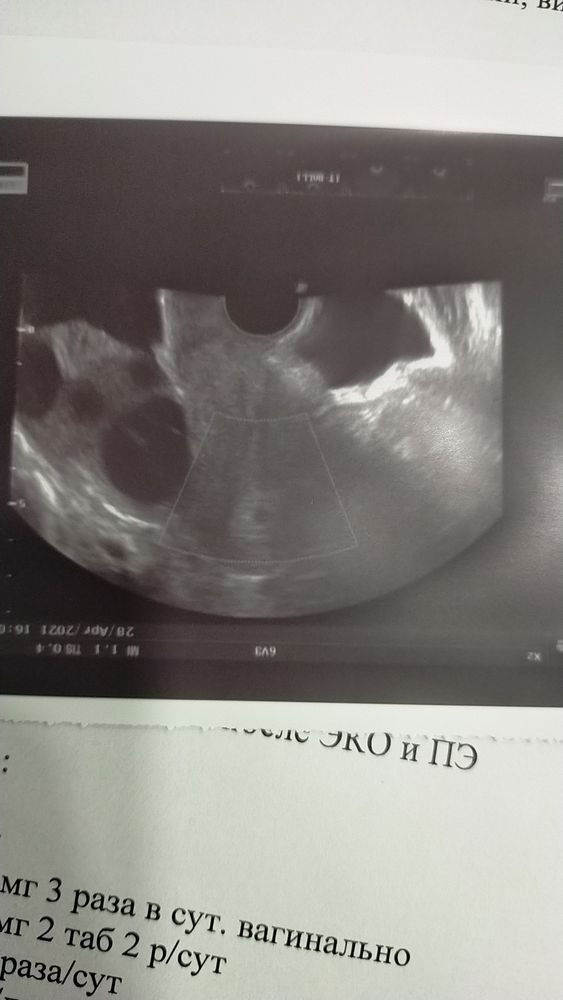

Наше первое узи!

Я БЕРЕМЕННА !Всем привет! Ну что,вот мы и прошли наше первое узи,мы ещё совсем крохотные, увидели пока только ПЯ ,срок по месячным 4 недели и 6 дней. Расти малыш,мы тебя ждём и любим!